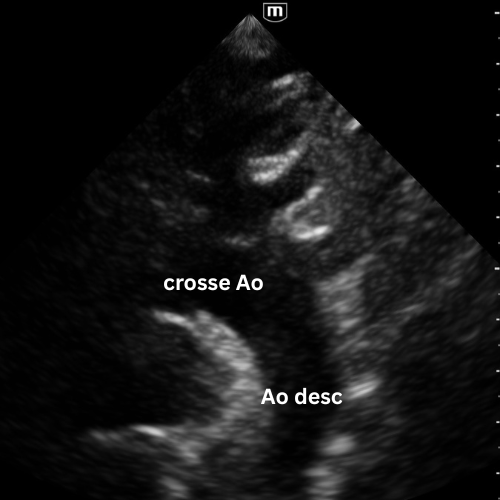

🔹 Vue Suprasternal

→ L’aorte est-elle normale ?

Placer la sonde dans la fosse jugulaire, marqueur vers la tête, légèrement à gauche.

Diriger le faisceau vers la crosse aortique.

Cette vue montre la portion ascendante, la crosse et parfois le début de l’aorte descendante.

Elle permet de détecter :

- une dilatation pathologique (> 40 mm) ;

- une flap de dissection mobile dans la lumière aortique ;

- un flux turbulent en Doppler couleur suggérant une brèche intimal.